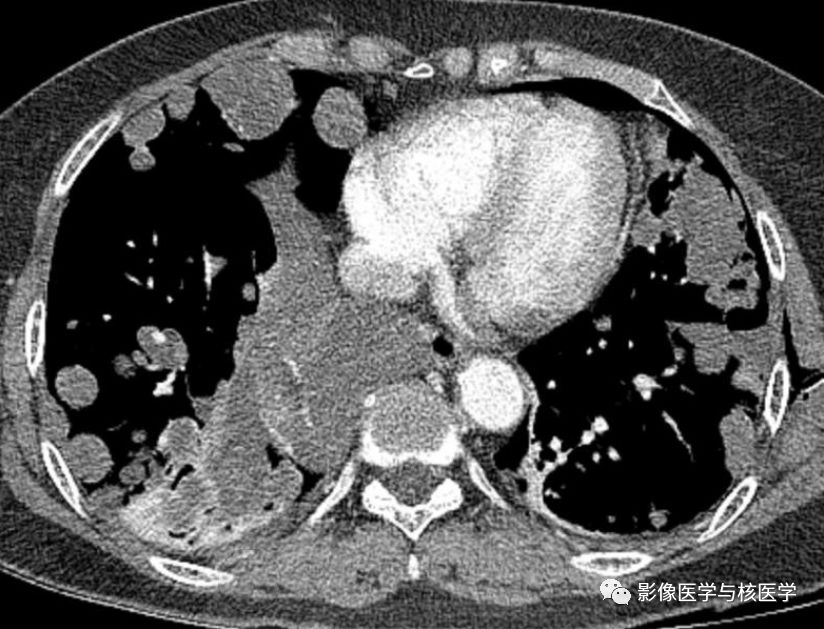

图2 胸部CT增强

Figure 2-4. On chest CT after chest tube insertion in left hemithorax, there are multiple nodules and masses with/without cavity in both lungs.

图2-4.胸部CT显示左侧气胸置管后,两肺多发结节或肿块伴或不伴空洞。